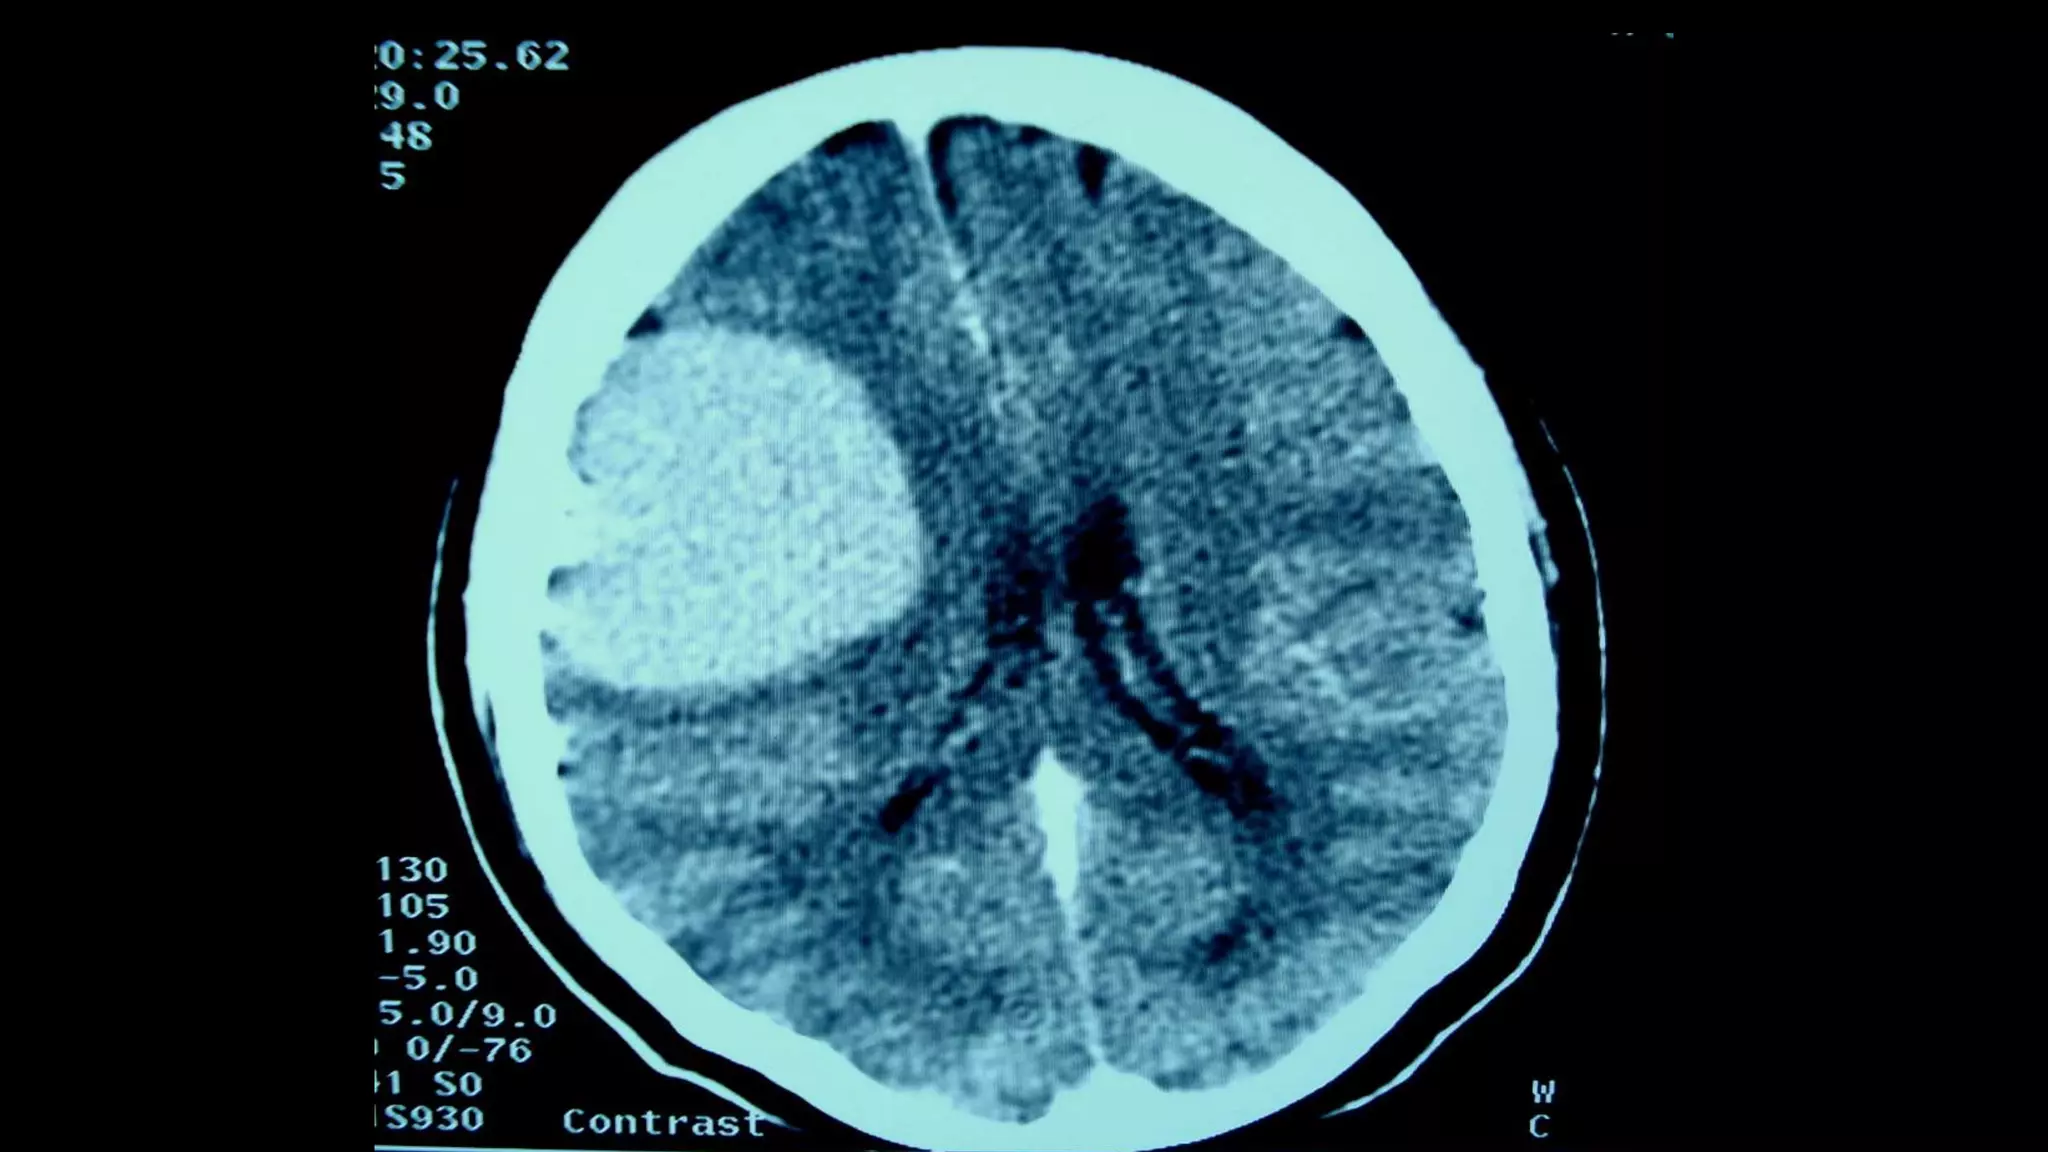

Hemiparesis with facial weakness: brain CT scan or brain MRI, with or

NB: Urgent non-contrast brain CT scan is the most suitable imaging

modality in patients with acute hemiparesis because of its availability in

Emergency Departments (usually), and it is rapid (the period of the test

is very brief (compared to MRI). Drawback: poor visualization of

posterior fossa structures because of boney artifacts, except in

posterior fossa hemorrhages.

Paresis, where? Hemiparesis withfacial weakness: brain CT scan or brain MRI, with or without contrast. Hemiparesis without facial weakness: Brain/upper cervical MRI, with or without contrast. NB: Urgent non-contrast brain CT scan is the most suitable imaging modality in patients with acute hemiparesis because of its availability in Emergency Departments (usually), and it is rapid (the period of the test is very brief (compared to MRI). Drawback: poor visualization of posterior fossa structures because of boney artifacts, except in posterior fossa hemorrhages. Paraparesis: dorsal spine MRI, with or without contrast or in some cases, brain/cervical MRI (with or without contrast).